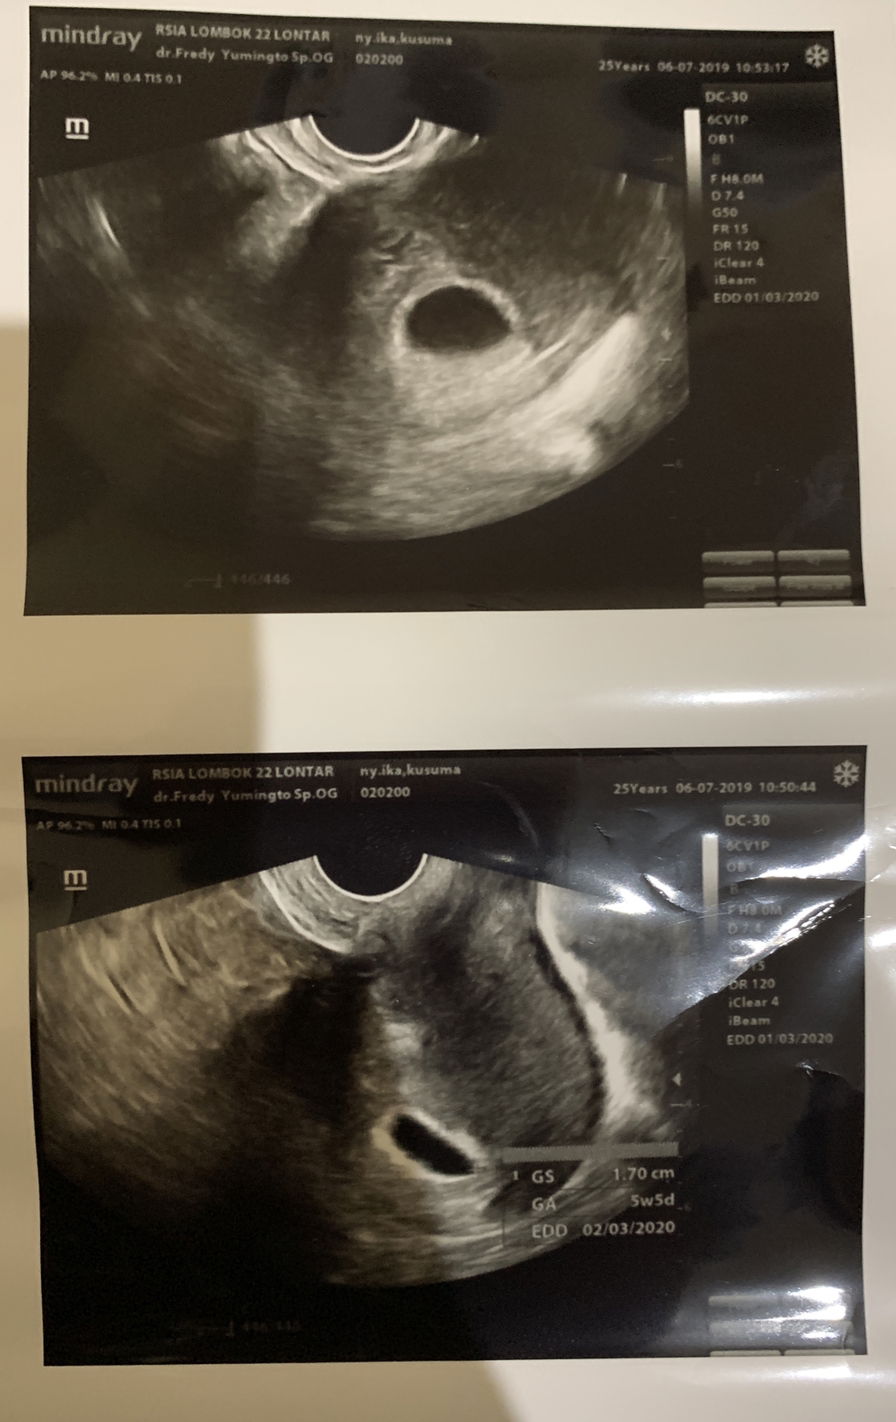

Selamat pagi buibu.. Sebelumnya saya mengucapkan banyak terimakasih utk ibu2 yg sdh memberikan masukan utk mencari second opinion di postingan saya yg pertama waktu itu. Alhamdulillah saya sdh mencari second opinion di sebuah klinik yg banyak di recom sama ibu2 di area surabaya timur. Dan kebetulan sekali tempatnya dekat sekali dgn rumah mertua. Awalnya saya dan suami tdk yakin krn klinik ini kecil, pembayaran hanya bs cash dan lagi antriannya banyak bgt buka jam 3 sore selesainya kadang sampai jam 12 malam lebih saking ramenya. Namanya iktiar ya, saya dan suami antri jam 5 sore baru ditangani jam set 10 malam. Dokternya humble dan tdk beribet. Langsung disuruh bebaring dan di cek dan hasilnya alhamdulillah babynya ada, detak jantungnya ada, dan dia berkembang baik. Dia ada di pojokan gitu buibu? Saya dan suami waktu itu bener2 excited dan dokternya blg bulan depan di ultrasound detak jantungnya. Dan saya diberikan vitamin tanpa penguat kandungan utk sebulan kedepan. Sedikit cerita, sebelumnya saya rutin periksa di rsia lombok dua dua, pemeriksaan terakhir disana usia kehamilan 5w5d pd tgl 06 juli 2019 waktu itu dokternya blg janinnya gak ada, saya dan suami benar2 down saat itu sampai sempat hampir bertengkar hebat. Dokter beri waktu seminggu lagi kalau janin tdk ada, langsung divonis janin tdk berkembang dan akan dilakukan tindakan. Saya saat itu rasanya benar2 tdk bs terima krn menurut saya, semuanya baik2 saja dan saya jg tdk ada keluhan layaknya org keguguran dan lain sebagainya. Akhirnya stlh dapat masukan dari ibu2 yg ada di forum ini utk cari second opinion ke dokter lain dulu, pada tgl 11 juli 2019 saya periksa ke klinik yg dekat rumah mertua ini dan dinyatakan janinnya ada, berkembang baik dan ada detak jantungnya dgn usia kehamilan 6w1d saat itu. Sedikit bingung dgn usia kehamilan saya tapi over all saya dan suami bersyukur dgn hasil yg kami peroleh saat itu. Terimakasih banyak ya ibu2.. Sehat2 utk yg sdg hamil.. Saling mendoakan ya buibu☺️ Saya share ya ibu2, Foto sebelah kiri, pemeriksaan terakhir di rsia lombok dua dua Foto sebelah kanan, pemeriksaan second opinion di klinik masyitoh